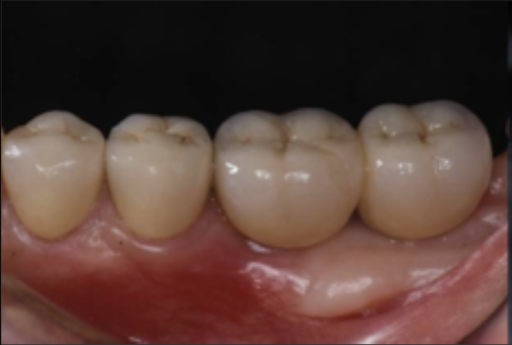

| 主訴 | 全顎治療希望、下の奥の歯が無いので全く噛めない。綺麗で噛めるようになりたい |

| 治療内容 | 下顎臼歯部欠損放置のため、臼歯部においてスペースがないため、全顎治療を行い咬合再構成を行う。 早期においてインプラント治療、咬合関係を模索した後、全顎にわたりセラミックによる補綴治療、その後メインテナンスに移行 |

| 治療費 | 5,410,000円(税込)(インプラントすべて含む) |

| 治療期間 | 1年8ヶ月 |

| 治療回数 | 80回 |

| 想定されたリスク | 食いしばり(パラファンクション)によるセラミックの破折、歯の破折 |